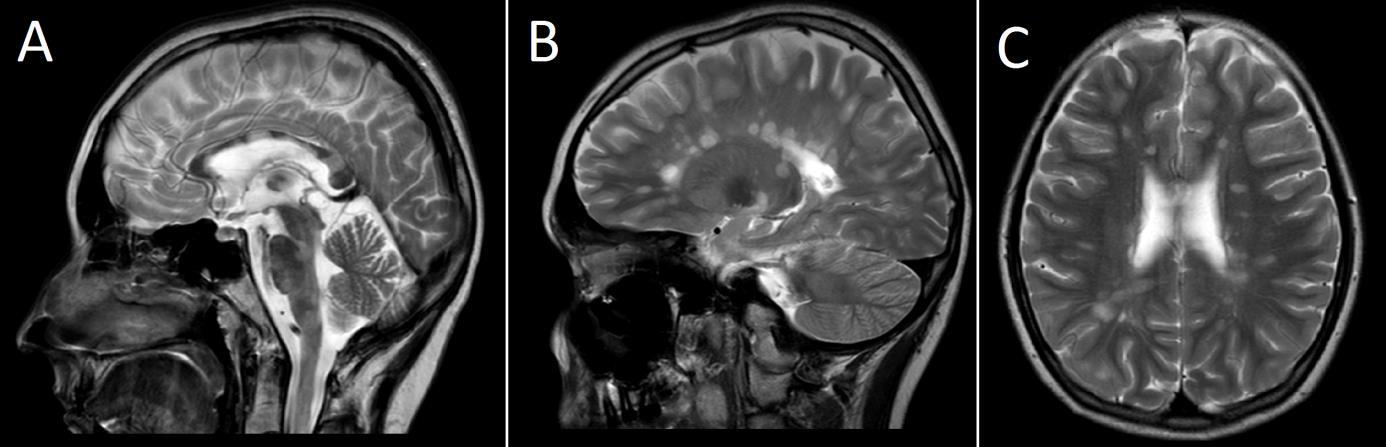

W diagnostyce neurologicznej ważną rolę odgrywają badania neuroobrazowe. Poniższe obraz MR głowy u 16-letniej chorej mogą odpowiadać zmianom w przebiegu: